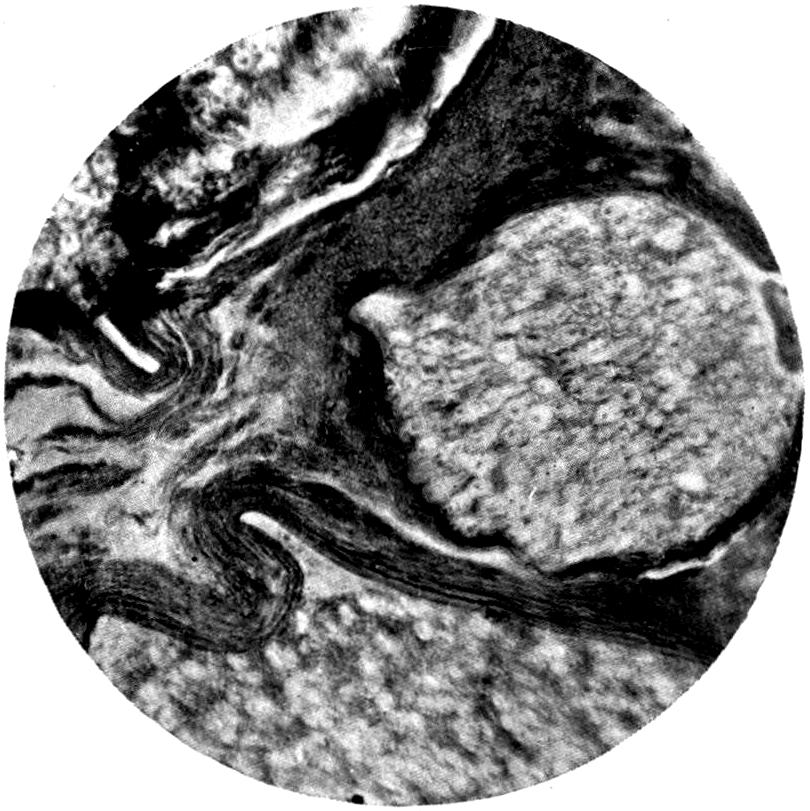

Plate III. 95